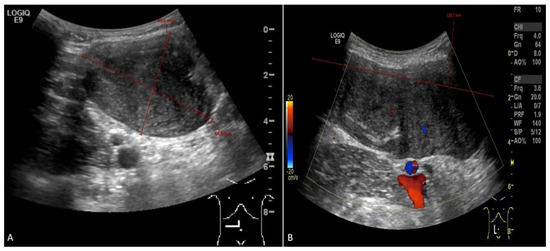

When the patient turned 26 (6 years after the surgery), she developed a desmoid tumor sized 12.0 × 4.6 × 6.6 cm on abdominal ultrasound scan (Figure 1) and 8.8 × 4.8 × 15.3 cm on MRI scan (Figure 2) in the anterior abdominal wall on the right side close to the previous trocar point of incision after laparoscopic surgery for FAP and transient-relieving stomy. This was primarily suspected to be sarcoma or a desmoid tumor. A core-needle biopsy was performed confirming the diagnosis of desmoid fibromatous tumor (Figure 3). The tumor board considered the situation as stable, with the possibility for partial spontaneous regression. As the risk for recurrence was assessed to be 50%, no surgery was performed, and she was referred for follow-up with new MRI control in about 3 months. During this follow-up period, she became pregnant and underwent a provoked medical legal abortion in week 6.

Figure 1.

Abdominal ultrasound ((A)—transverse view; (B)—longitudinal view) picture of desmoid tumor, sized 12.0 × 4.6 × 6.6 cm on the first diagnosis.